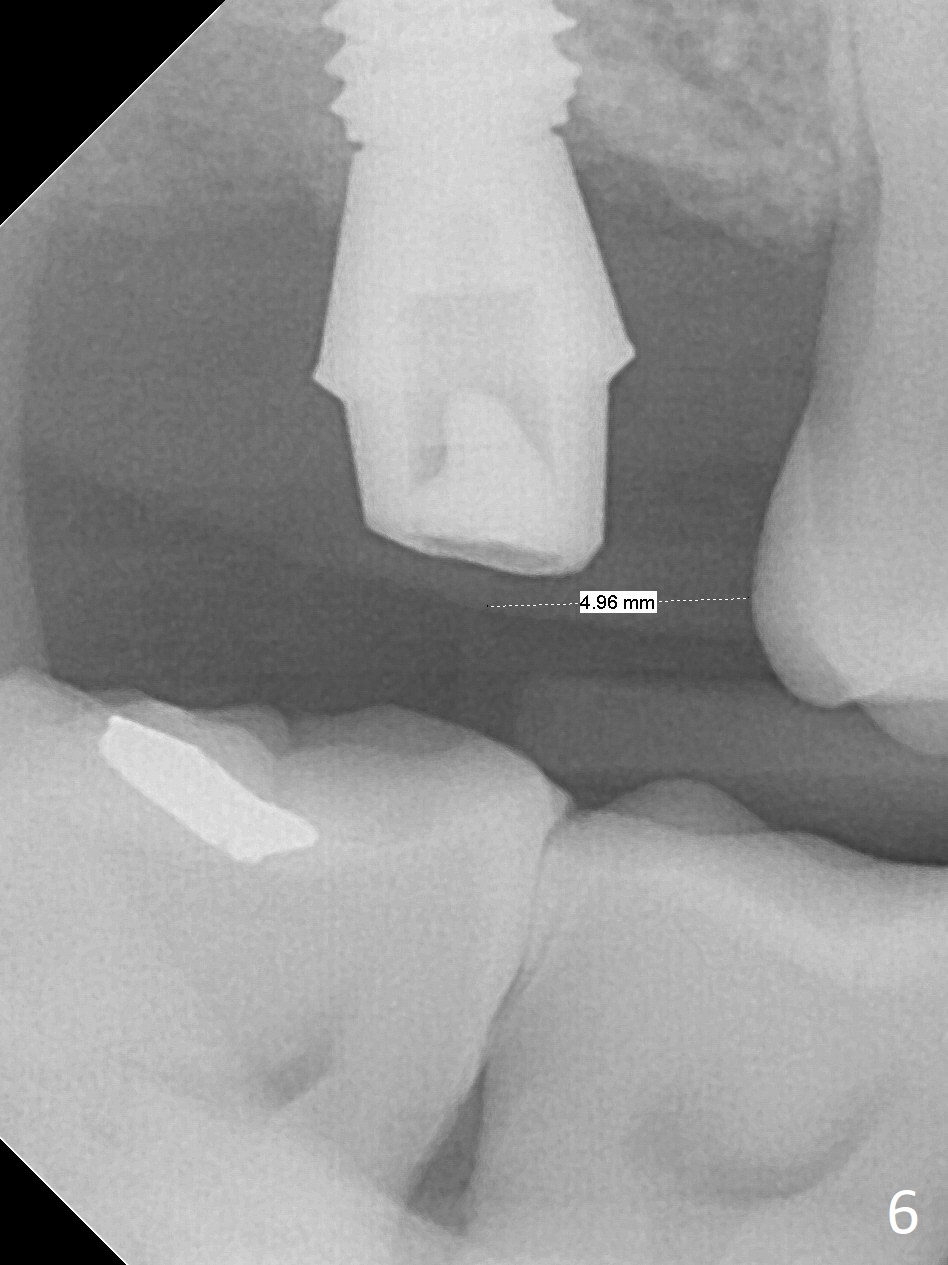

After extraction of the 3rd molar with mesial periodontal defect, osteotomy for 2nd molar implant is initiated in the mesial slope of the 3rd molar socket (Fig.1 red dashed line). When osteotomy is finished with IS drills and sinus lift with Magic Sinus Lifter (S-reamer with 11 mm stopper being short), a 4x10 mm dummy implant is placed with ~ 4 implant thread exposure (Fig.3). Following use of Lindamann bur to move osteotomy mesial and larger drill, a 4.5x10 mm implant is placed with 5-7 implant threads exposed distally (Fig.4,7 (~ 50 Ncm)). The bucco(B)-palatal(P) extent of the implant thread exposure is larger (Fig.5) than that associated with the 4 mm dummy implant (data not shown). The exposed implant surface is covered with Vera Graft (Fig.7*), Collagen plug and an immediate provisional after adjustment of abutment height (Fig.6,7). The bone density distal to the implant is low 3 months postop (Fig.8,9 CBCT) and 3.5 months postop (Fig.10,11). The permanent crown is cemented nearly 4 months postop. The distal cortical bone contacts the implant (Fig.12 ^), while the mesial bone increases in density (*) 2 years postop.